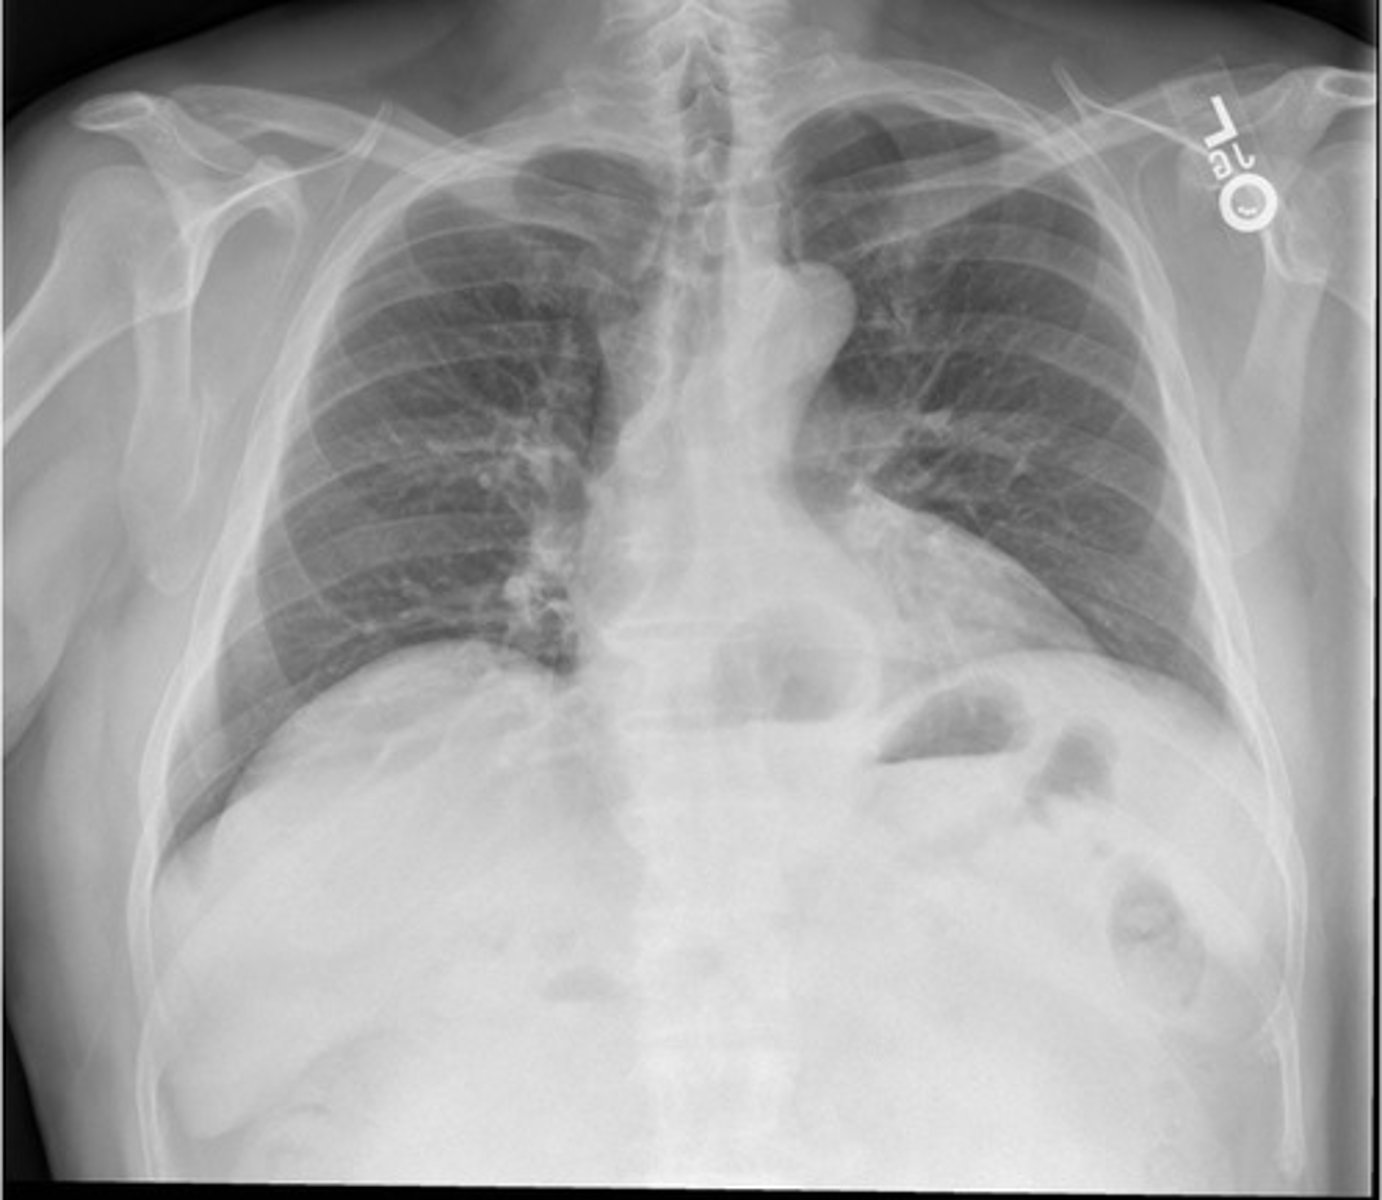

Hiatal hernia CXR

Hiatal hernia CXR (Pic 2)